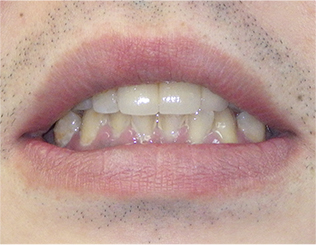

- ブリッジ 症例写真 B-0093スタンダードジルコニア9本、スタンダードジルコニア7本 男性モニターの方です。

Before

After詳細はコチラ

セラミック法によるブリッジ治療の症例

- No. B-0093

施術 スタンダードジルコニア9本、スタンダードジルコニア7本 - コメント

この方は前歯の歯並びと奥歯の虫歯、欠損の治療を希望されました。

前歯の歯並びはセラミック法で治療しました。

奥歯の欠損はブリッジで治療しました。

また、下の前歯も歯周病で1本抜歯になりましたのでその部分もブリッジ治療しています。

当院ではこの様にいろいろな歯のお悩みがあっても同時進行で治療する事が可能です。